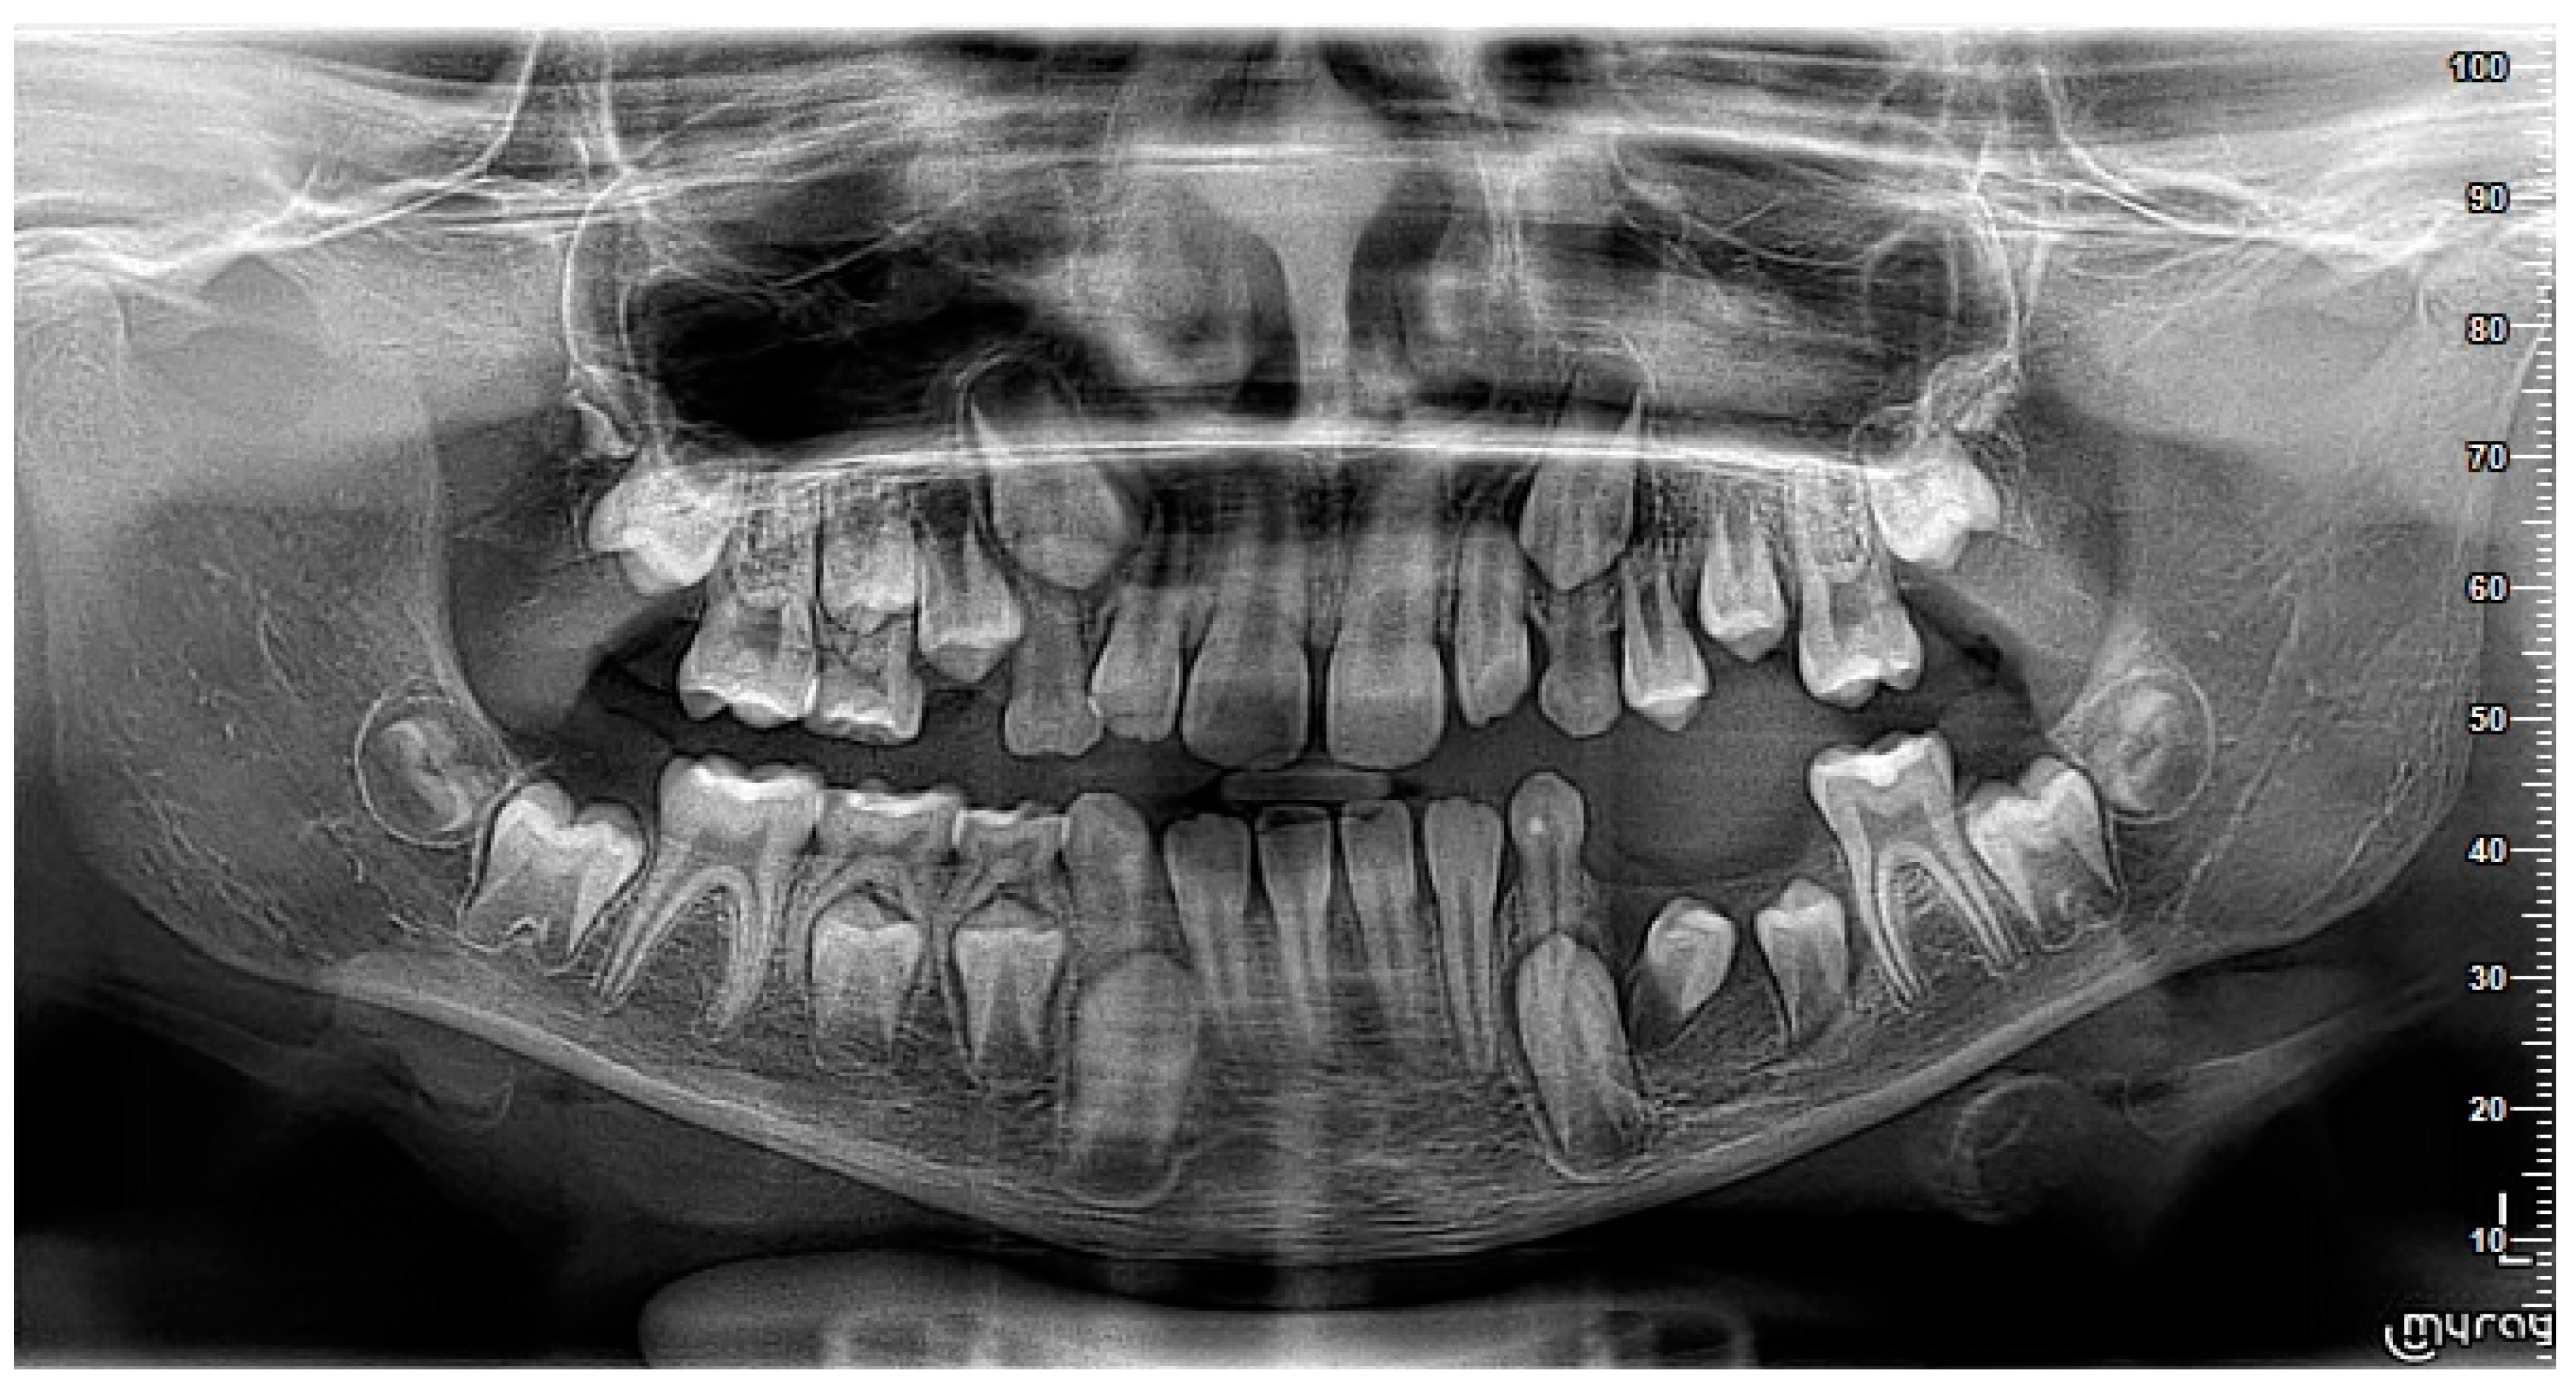

2. Case Report